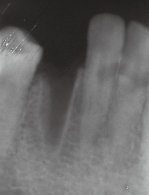

左下3缺失,牙龈略红肿,近远中距离可,对颌无伸长 X线示牙槽窝内空虚